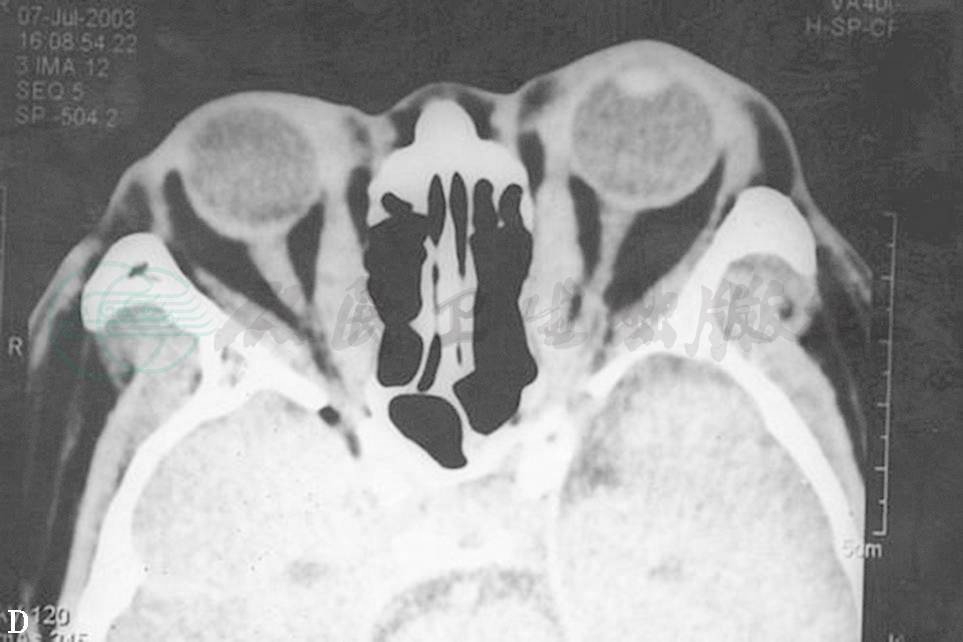

CT扫描均显示眼球突出的原因分为3种:①眶内脂肪含量增加,而眼外肌无明显增大(图3A、B);②眶内脂肪含量增加,眼外肌也增大(图3C、D);③眶内脂肪含量增加不明显,眼外肌增大明显(图3E、F)。

图3眼球突出

A.双眼球明显突出 B.眼眶CT轴位扫描见眼眶脂肪明显增多,眼外肌未增大 C.双眼球突出、呈上转位 D.眼眶CT轴位扫描见眼眶脂肪增多、眼外肌增大 E.双眼球突出 F.CT轴位扫描见眼外肌明显增大,眼眶脂肪不增多